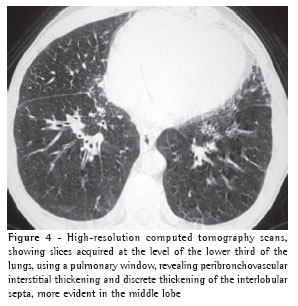

Overall, ground-glass opacities and thickening of the interlobular septa were the most common findings, occurring in 100% of the cases (Figures 1 and 2).

The thickening of the interlobular septa was bilateral in thirteen cases (Figures 1-4) and unilateral in two, also in the patients with fibrosing mediastinitis. In all cases, the thickening was of the smooth type.

Consolidation was detected in only five (33%) of the patients (Figures 2 and 5). All of the patients presented bilateral consolidations, In two cases, the distribution was asymmetric, with a 'bat-wing' aspect, and predominant in the upper right lobe (cases of mitral valve chordae rupture) (Figure 5).

Pleural effusion was the third most common tomographic finding overall and was the most common nonparenchymal finding, being found in 13 patients (87%), predominantly in the bilateral form (n = 11) (Figures 1-3).

When the fluid reaches the alveolar space, characterizing the last phase of hydrostatic edema (alveolar edema), small nodules form. These are accompanied by acinar areas, which are prone to confluence, forming pronounced, well-defined bilateral consolidations. Probably due to the gravitational effect, these consolidations are predominantly found in the

central and lower potions of the lungs.(1,3)

Hydrostatic pulmonary edema that occurs suddenly can present as a

distinct pattern known as a 'bat-wing' or 'butterfly-wing' pattern. The increase in pressure occurs abruptly, with a rapid passage from the first phase (interstitial) to the second (alveolar), and the first phase is therefore not seen radiologically. This aspect occurs mainly in cases of acute myocardial infarction, chordal rupture, infarction of the papillary muscles or renal failure.(3,12)

We observed the 'bat-wing' distribution of consolidations in two patients with acute rupture of the mitral chordae, one due to myxomatous degeneration and the other due to acute myocardial infarction. According to some authors,(1) this 'bat-wing' aspect is only seen in cases of acute hydrostatic pulmonary edema. The imaging aspect is that of a consolidation that spares the lung periphery. In the cases of rupture of the mitral chordae, the consolidation was asymmetric and predominantly in the upper right lobe. Other authors(18) reported four cases of mitral regurgitation with asymmetric edema in the upper right lobe. Still other authors(19) determined that the frequency of upper right lobe involvement in patients with mitral reflux was 9%. The regurgitated blood moves to the posterior wall of the left atrium, where the entrance of the upper right pulmonary vein is located, resulting in more pronounced edema within the region drained by this vein.(18,20)